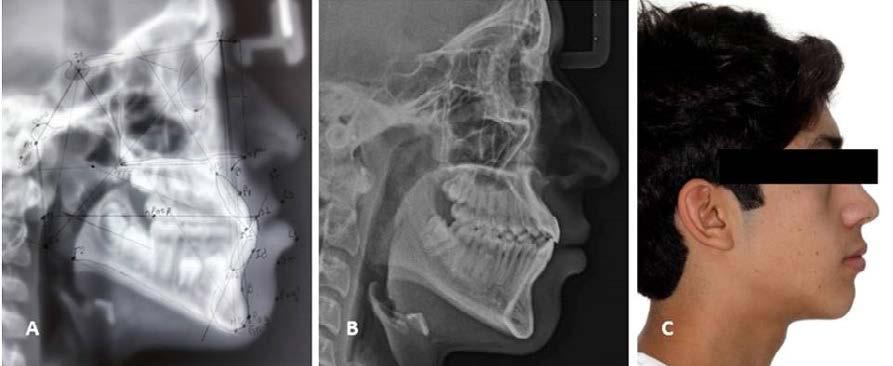

Figura 1. Estudios de inicio. A) Radiografía lateral de cráneo. B), C) y D), Fotografías extraorales (frente, frente con sonrisa y perfil). E), F), G), H), e I. Fotografías

intraorales (lateral derecha, frontal, lateral izquierda, oclusal superior, oclusal inferior).

Con los estudios realizados se confirmó clase III dental, depresión del tercio medio en la cara, observándose una discrepancia en el tamaño del maxilar contra la mandíbula y ausencia del OD 63, radiográficamente el OD 23 aún sin erupcionar (Figura 1).